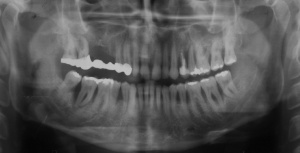

Aufgrund der parodontalen Destruktion, die letztlich erst mit dem intraoperativen Befund dreidimensional beurteilt werden konnte, mussten die Zähne 17, 26 und 27 als langfristig nicht erhaltungswürdig beurteilt werden. Da mit ihrem Verlust auch keine ausreichenden natürlichen Pfeiler mehr für einen definitiven festsitzenden Zahnersatz zur Verfügung standen, wurde eine implantatprothetische Versorgung mit zwei Implantaten in regio 15, 16 und drei Implantaten in regio 24, 25, und 26 geplant. Die Implantation und die entsprechenden präimplantologisch-augmentativen Maßnahmen wurde in der kieferchirurgischen Ambulanz (FU VIIb, Leiter Prof. Dr. Dr. K.O. Henkel) durchgeführt. Eine zwingende Indikation zur Versorgung der Freiendsituation ab 36 und der Schaltlücke bestand nicht, sodass in Übereinstimmung mit dem Patienten für den Unterkiefer kein Zahnersatz geplant und angefertigt wurde. Nach Wiedervorstellung im Oktober 2003 wurde die implantatprothetische Versorgung mit der Eingliederung der implantatgetragenen Kronen 15, 16, 24, 25, und 26 im November 2003 abgeschlossen. Mit der Eingliederung von Einzelkronen an 14, 13 und 23 im Februar 2004 wurde die Behandlung insgesamt abgeschlossen (s. Abb. 6). Die ursprünglich angedachte Extraktion der Molaren 17 und 28 wollte der Patient nicht mehr durchführen lassen.

Ab dem Februar 2004 wurde der Patient zur Sicherung des Behandlungserfolges in das in der FU VIIa – Zahnmedizin seit 1996 praktizierte Recallsystem aufgenommen. Diese Erhaltungstherapie beinhaltet die bereits erwähnten Maßnahmen der Unterstützenden Parodontitistherapie (UPT). Aufgrund dienstlicher Erfordernisse (u. a. immer wieder Seefahrten des Patienten) konnte der zunächst geplante Abstand von vier Monaten nicht immer eingehalten werden. Ein Abstand von ca. sechs Monaten konnte jedoch trotz der teilweise schwierigen Rahmenbedingungen realisiert werden. Am Zahn 44 kam es im Jahr 2006 zu einem Rezidiv, sodass an diesem Zahn im September 2006 eine Lappenoperation durchgeführt wurde. Der intraoperativ vorgefundene tiefe cirkuläre vertikale Defekt führte zur Einschätzung einer langfristig fraglichen Prognose von 44. Im Zuge der weiteren Erhaltungstherapie zeigten sich bis auf 44 die parodontalen und periimplantären Gewebe völlig unauffällig: So betrugen die Sondiertiefen bei entzündungsfreien klinischen Verhältnissen durchweg zwei bis drei Millimeter. Auch radiologisch zeigten sich keine Auffälligkeiten. Es gab keine Progredienz der ehemaligen parodontalen Erkrankung, die Osseointegration der Implantate zeigte keine Veränderungen (s. Abb. 7). Erhöhte Sondiertiefen verblieben lediglich am Zahn 44. Nachdem sich trotz regelmäßiger Nachsorge an 44 keine Entzündungsfreiheit der marginalen Gingiva erzielen ließ und die Zahnlockerung von 44 zunehmend stärker wurde, erfolgte im Jahre 2010 die Entfernung des Zahnes und der Ersatz durch eine implantatgetragene Krone (s. Abb. 8). Die Erhaltungstherapie wurde fortgeführt, Behandlungsmaßnahmen über die Inhalte der UPT hinaus waren bis zur Entlassung des Soldaten im Jahre 2012 nicht erforderlich. Der Patient blieb jedoch auch nach der Entlassung aus dem aktiven Dienst Patient des Hauses, sodass die Erhaltungstherapie in der FU VIIa – Zahnmedizin fortgeführt werden konnte. Im April 2013 stellte sich der Patient mit Beschwerden am Zahn 45 vor, der Zahn wies zudem eine Lockerung des Grades II auf. Die durchgeführte Röntgendiagnostik (s. Abb. 9) zeigte eine Wurzelfraktur im apikalen Wurzeldrittel, ein Zahnerhalt von 45 war nicht möglich und der Zahn wurde noch in gleicher Sitzung entfernt. Zur Versorgung der Lücke wären verschiedene prothetische Lösungen möglich gewesen. Letztlich fiel die Entscheidung zugunsten eine Extensionsbrücke von regio 45 auf 48. So konnte die Implantatkrone 44 belassen und mit dem Lückenschluss mittels einer vergleichsweise einfachen und schnellen prothetischen Versorgung auch die Schaltlücke 46 geschlossen werden. Der Patient befindet sich nach wie vor in der FU VIIa in der Erhaltungstherapie, die Fotos zeigen den aktuellen klinischen Befund in der Aufsicht des Ober- und Unterkiefers (s. Abb. 10, 11).

Aufgrund der fortgeschrittenen parodontalen Vorerkrankung musste mit der Planung und der Herstellung des definitiven Zahnersatzes lange gewartet werden. Zunächst wurden im Mai 2001 die erneuerungsbedürftigen Kronen der prognostisch als günstig beurteilten Zähne 11 und 21 erneuert. Im April 2002 wurde die Versorgung der Schaltlücke in regio 36 mit der Einbringung eines dentalen Implantats in regio 36 begonnen, die mit der Herstellung der implantatgetragenen Krone im November 2002 abgeschlossen wurde (s. Abb. 15). Das Langzeitprovisorium 23 auf 28 wurde im Oktober 2004 durch eine definitive Brücke von 23 auf 28 ausgetauscht.